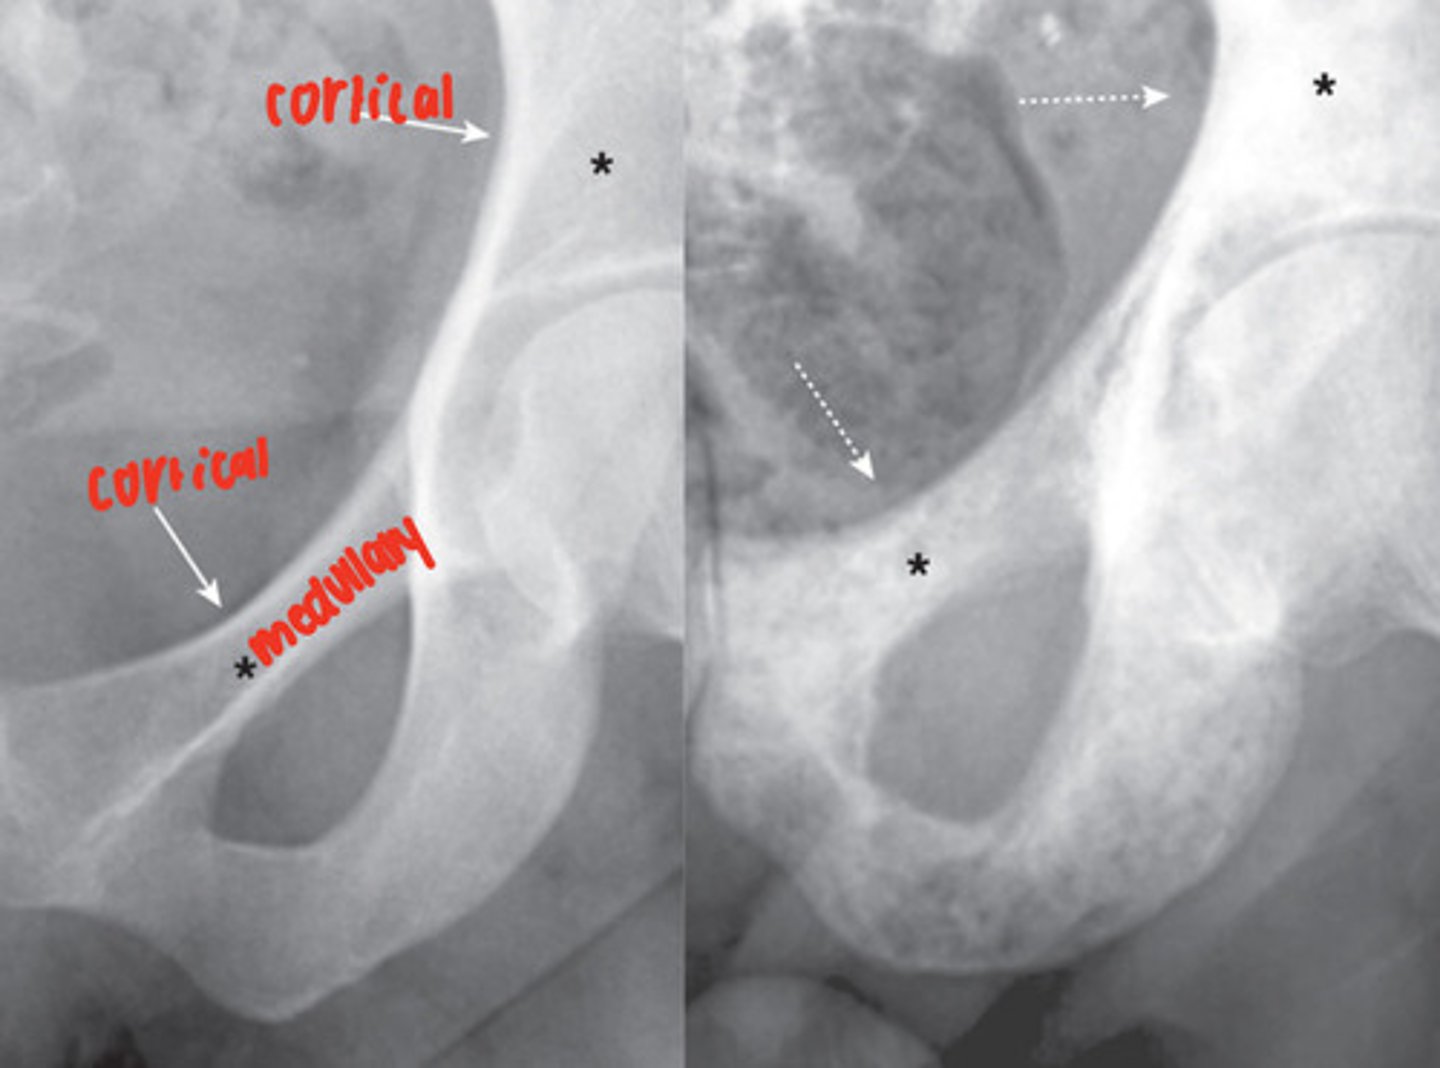

osteoblastic diseases

increase bone density, seen as opaqueness (sclerosis), abnormal cortico-medullary junction, possible pathological fractures of long bone

ex. osteosarcoma, osteoblastic metastatic disease, avascular necrosis of bone, paget disease

osteolytic diseases

decrease bone density, lower density of medullary cavity, accentuation of cortex, compression of vertebral bodies, pathologic fractures

ex. osteoporosis, hyperparathyroidism, osteolytic metastatic disease, multiple myeloma, osteomyelitis

osteolytic metastatic disease

malignancy spread causes bone destruction, mainly medullary cavity but cortex can be involved

MRI- excellent at demonstrating status of the medullary cavity

- irregularly shaped, lucent bone lesions